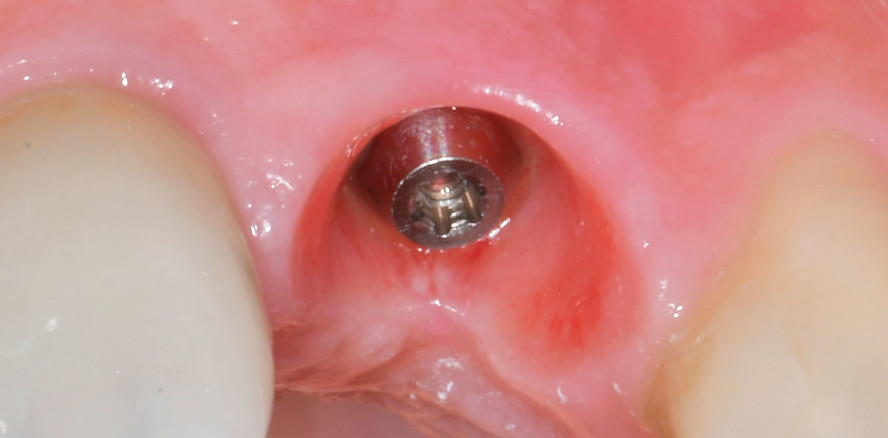

Radiologisch war ein signifikanter Knochenabbau um das Implantat zu verzeichnen (Abb. 2). Die klinische Untersuchung zeigte klassische Anzeichen einer periimplantären Entzündung: Bluten auf Sondieren (BOP+), erhöhte Sondierungstiefen (ST) und eine lokale Schwellung der Mukosa (Abb. 3–5). Das primäre Ziel war es, den Entzündungsprozess nicht chirurgisch zu stoppen und ein biologisches Milieu zu schaffen, das eine langfristige Stabilität ermöglicht. Der Implantataufbau wurde derzeit am Halsbereich zu dick ausgearbeitet und wies aus diesem Grund kein optimales Emergenzprofil auf. Nach der Eingliederung der definitiven prothetischen Versorgung kann es – insbesondere bei dicken suprakrestalen Weichgeweben – vorkommen, dass sich das Weichgewebe an die Kronenkontur adaptiert, was biologisch nicht immer gut toleriert wird. In der Folge kann es zu einer lokalen entzündlichen Reaktion kommen. Aus diesem Grund war zudem eine Umgestaltung der Krone vorgesehen.

Die erste Säule der Behandlung („Clean“-Phase) bildete die submarginale Instrumentierung unterstützt durch das Reinigungsgel. Da eine rein mechanische Reinigung oft nicht ausreicht, um den Biofilm in den Mikrostrukturen der Implantatoberfläche vollständig zu entfernen, wurde nach dem Entfernen der Krone adjuvant das Reinigungsgel (Perisolv) eingesetzt.